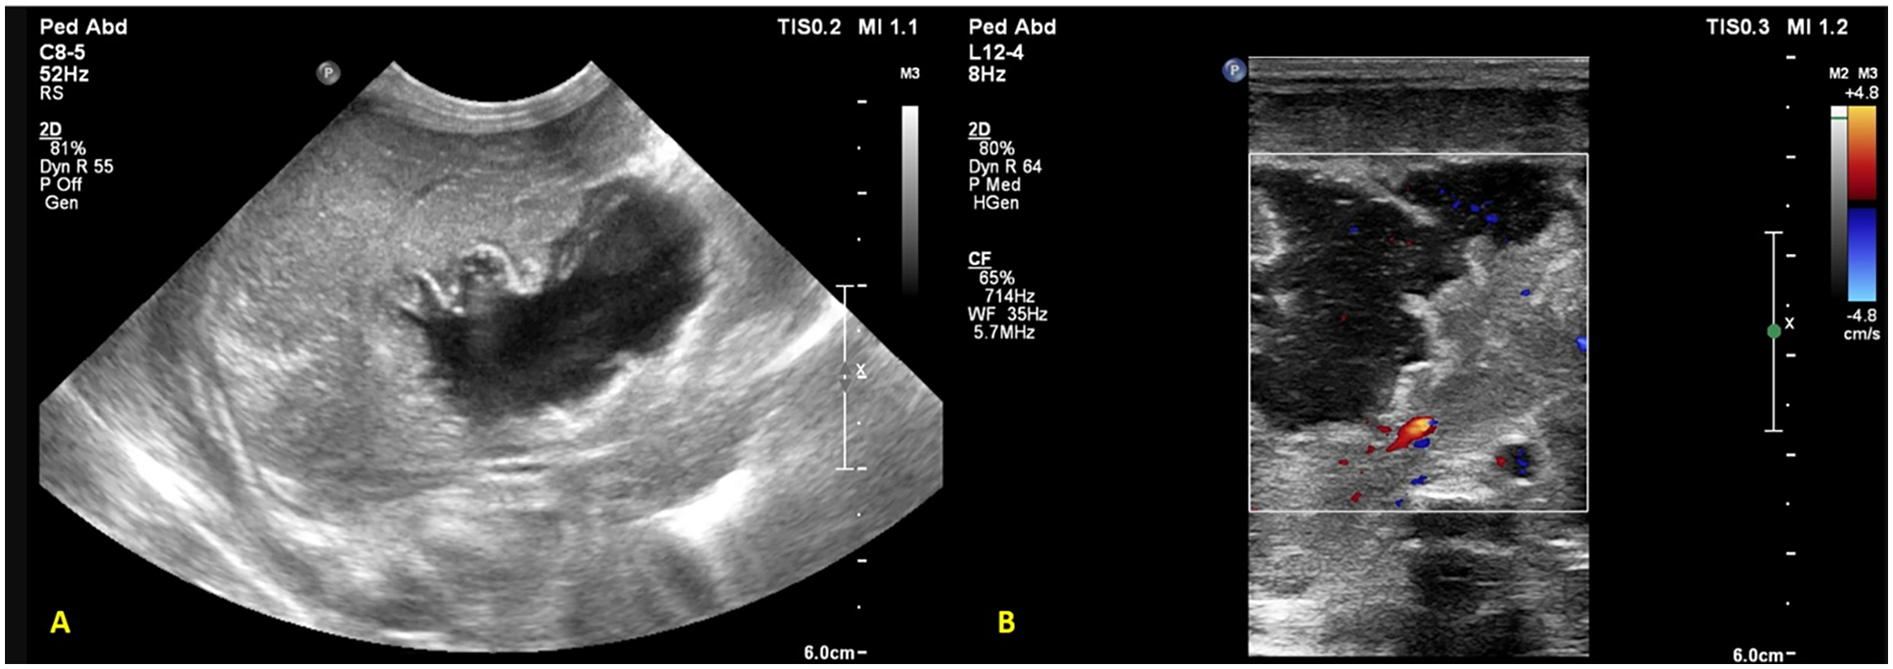

An extremely preterm (27 + 5 weeks), VLBW (1,005 g), male neonate was born to a gravida 2 mother via spontaneous vaginal delivery, with a maternal history of PPROM of 9 h. In the NICU, the neonate received mechanical ventilation and surfactant therapy for respiratory distress within one hour of birth. The UAC and UVC were secured. On check x-ray, the UVC tip was found at the level of the diaphragm, T9-T10 (Figure 5A). First-line antibiotics and TPN were initiated. The neonate was extubated at HOL 24 to NIV support. The UAC was removed on day 3. The infant was reintubated at HOL 70 for worsening respiratory distress on NIV support. A FnECHO was suggestive of a hemodynamically significant PDA and paracetamol was started for PDA closure. A postintubation x-ray incidentally revealed a UVC tip in the liver (Figure 5B), which was adjusted to a low-lying position. The neonate was again extubated on DOL 6 and the UVC was removed on DOL 7. On DOL 9, the baby had abdominal distension associated with bilious aspirates; a sepsis workup showed rising levels of CRP and thrombocytopenia; antibiotics were upgraded further. Blood culture grew Sphingomonas paucimobilis and antibiotics were adjusted as per the sensitivity report. There was clinical improvement, and the neonate remained hemodynamically stable thereafter. On DOL 17, while performing a lung ultrasound for inability to wean NIV support, the neonatal trainee incidentally found a hyperechoic lesion in the right lobe of the liver, measuring 1.4 cm × 1.0 cm × 1.4 cm (Figure 5C). This was confirmed by the radiologist, and a differential diagnosis of liver hematoma or TPN extravasation was considered. The neonate is currently stable on CPAP and full feeds. A follow-up ultrasound on DOL 34 showed regression in the size of a lesion.

Figure 5

Plain chest and abdomen radiograph showing (A) a UVC tip at the level of the diaphragm (T9–10) (B) on day 3, the UVC tip shows migration to the T12 level, likely in hepatic parenchyma (C) liver POCUS showing a heteroechoic mass in the right lobe of the liver.

A preterm (GA 27 + 3 weeks) infant, weighing 1,120 g, was born to a gravida 2 mother via emergency cesarean section in view of antepartum hemorrhage and required delivery room intubation for resuscitation. The baby was transferred to the NICU, where it developed significant respiratory distress requiring mechanical ventilation. A chest x-ray showed a ground glass appearance of the lungs with air bronchograms, and surfactant was administered at 2 h of life. Umbilical venous and arterial catheters were secured and antibiotics commenced. The initial hemogram was normal. A second dose of surfactant was administered for high oxygen requirement, following which ventilator settings were weaned. On DOL 4, the neonate had an episode of pulmonary hemorrhage. Investigations revealed thrombocytopenia and a deranged coagulation profile. Blood products were administered, and the patient was placed on HFOV. Repeat blood cultures and endotracheal secretions grew Stenotrophomonas maltophilia, which was sensitive to fluroquinolones and ceftazidime; antibiotics were modified accordingly. The patient improved clinically. However, as thrombocytopenia persisted despite clinical improvement, adequate antibiotic coverage, and platelet transfusions, additional causes for thrombocytopenia were considered. A screening bedside ultrasound of the abdomen to screen for thrombosis in major vessels revealed an echogenic thrombus in the right and left portal vein, with a reformation of the distal portal vein (Figure 6). The umbilical lines were removed, and the antibiotics were continued for a total of 14 days. The patient was subsequently extubated and discharged on DOL 66. A repeat ultrasound abdomen prior to discharge showed normal flow through the portal vein.

Figure 6

Liver POCUS shows an echogenic thrombus (arrow) in the portal vein.